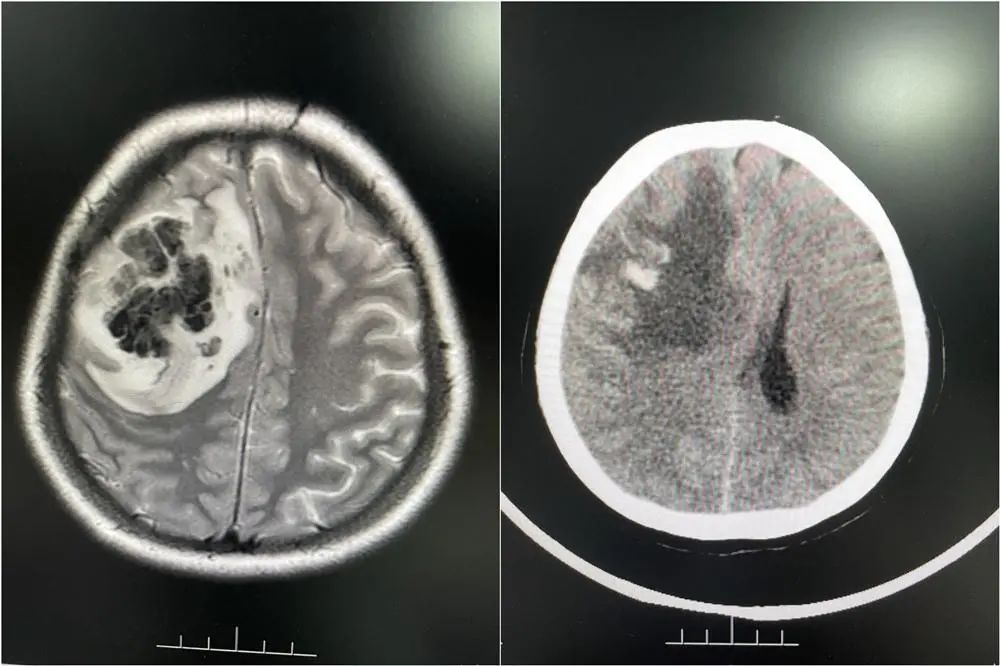

随后婷婷在当地医院查出右侧额叶占位性病变合并出血,医生怀疑是脑肿瘤卒中。陈女士说:“婷婷当时已经昏迷不醒,都剃了头发准备手术。”为寻求进一步诊疗,2月底,家人陪同婷婷来到广东三九脑科医院。

医院接诊医生仔细分析后,发现婷婷颅内病变不是脑肿瘤。结合病史和相关影像资料,该院神经内一科副主任匡祖颖初步怀疑是颅内静脉窦血栓,进一步完善全脑血管造影,证实是颅内静脉窦血栓形成合并出血 。